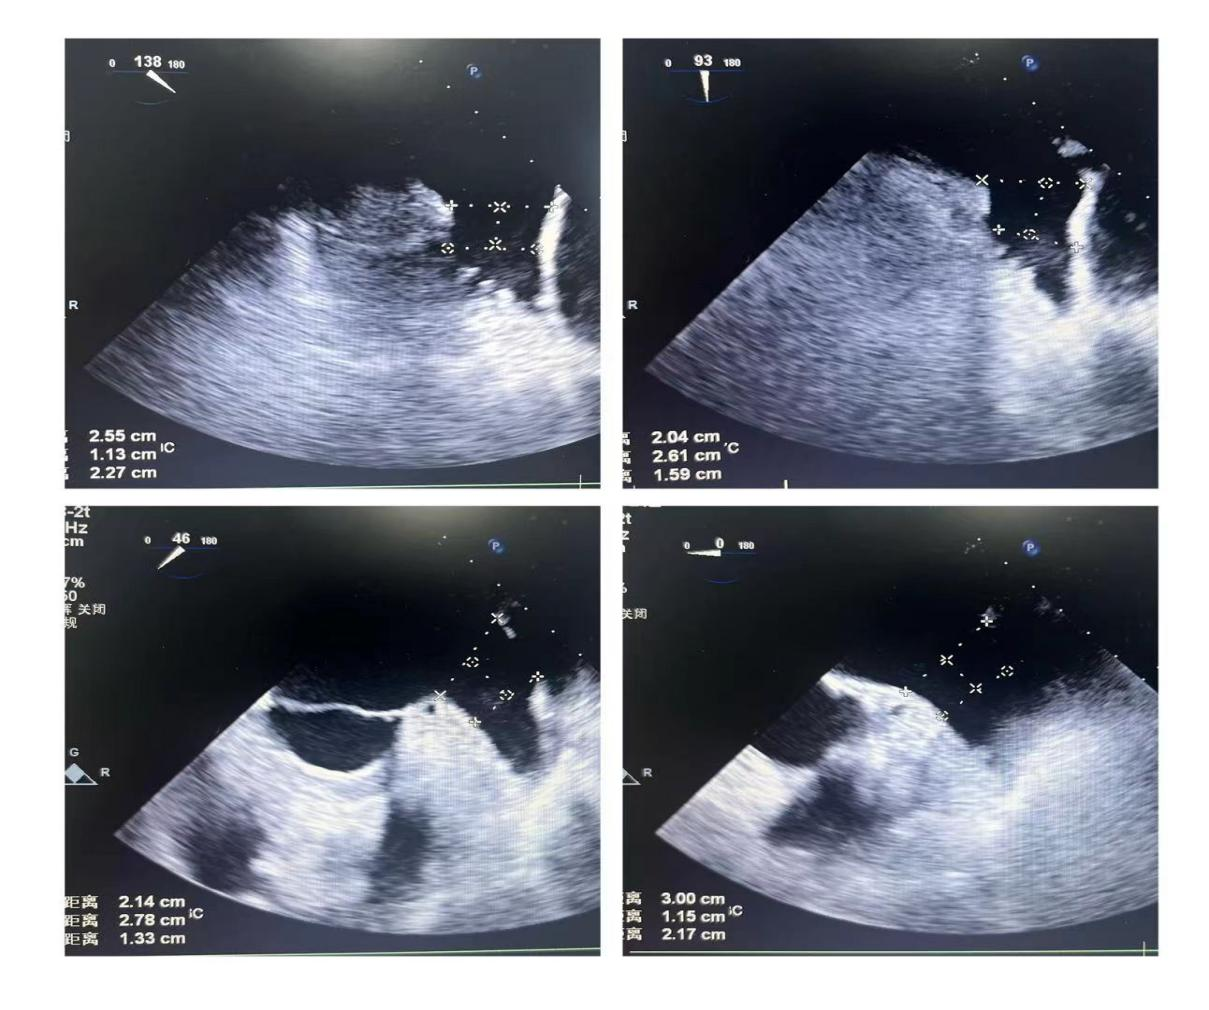

潘教授通过食道超声从4个不同的角度来观察患者左心耳的形态情况,显示心耳为反鸡翅型,位置较低,锚定区为23mm,封堵区为26mm。术者结合多年的临床经验,最终选用型号为LT-LAA-2632的LAmbre™左心耳封堵器对患者进行封堵。

▲(图:通过超声观察进行穿刺)

在食道超声引导下进行房间隔穿刺,由于心耳为反鸡翅型,穿刺位点需靠下靠前,潘教授先在90度双腔切面将定位靠下,再在45度主动脉短轴切面将定位靠前。穿刺成功后上导丝交换先健LAnavi™分段控弯导引系统送至心耳口部,经过A、B双弯的调整使得鞘管轴向与心耳同轴,获得理想封堵位置。然后推送钢缆释放出固定盘,锚定后退鞘释放出封堵盘。超声下观察贴合良好,无明显残余分流,牵拉测试稳定,即释放左心耳封堵器。释放后再次通过超声各个角度进行验证,封堵结果完美有效,整个过程一气呵成,手术取得了极大的成功。